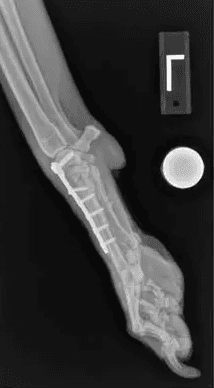

Partial Arthrodesis

A partial arthrodesis involves fusion of only some of the wrist or ankle, maintaining some range of motion and function of that wrist or ankle. Injuries that do not involve the tibiotarsal or radiocarpal joints are candidates for a partial arthrodesis. All cartilage between the affected joints are removed then filled with bone graft. A bone plate and screws is typically used to stabilize the bones while they fuse together.

Pancarpal/Pantarsal Arthrodesis

A complete arthrodesis involves fusion of the entire joint, eliminating all range of motion. A complete arthrodesis is necessary when the tibiotarsal or radiocarpal joints are affected. The cartilage is removed between all joints within the wrist or ankle then filled with bone graft. A specialized bone plate and screws are used to stabilize the bones until they fuse completely.